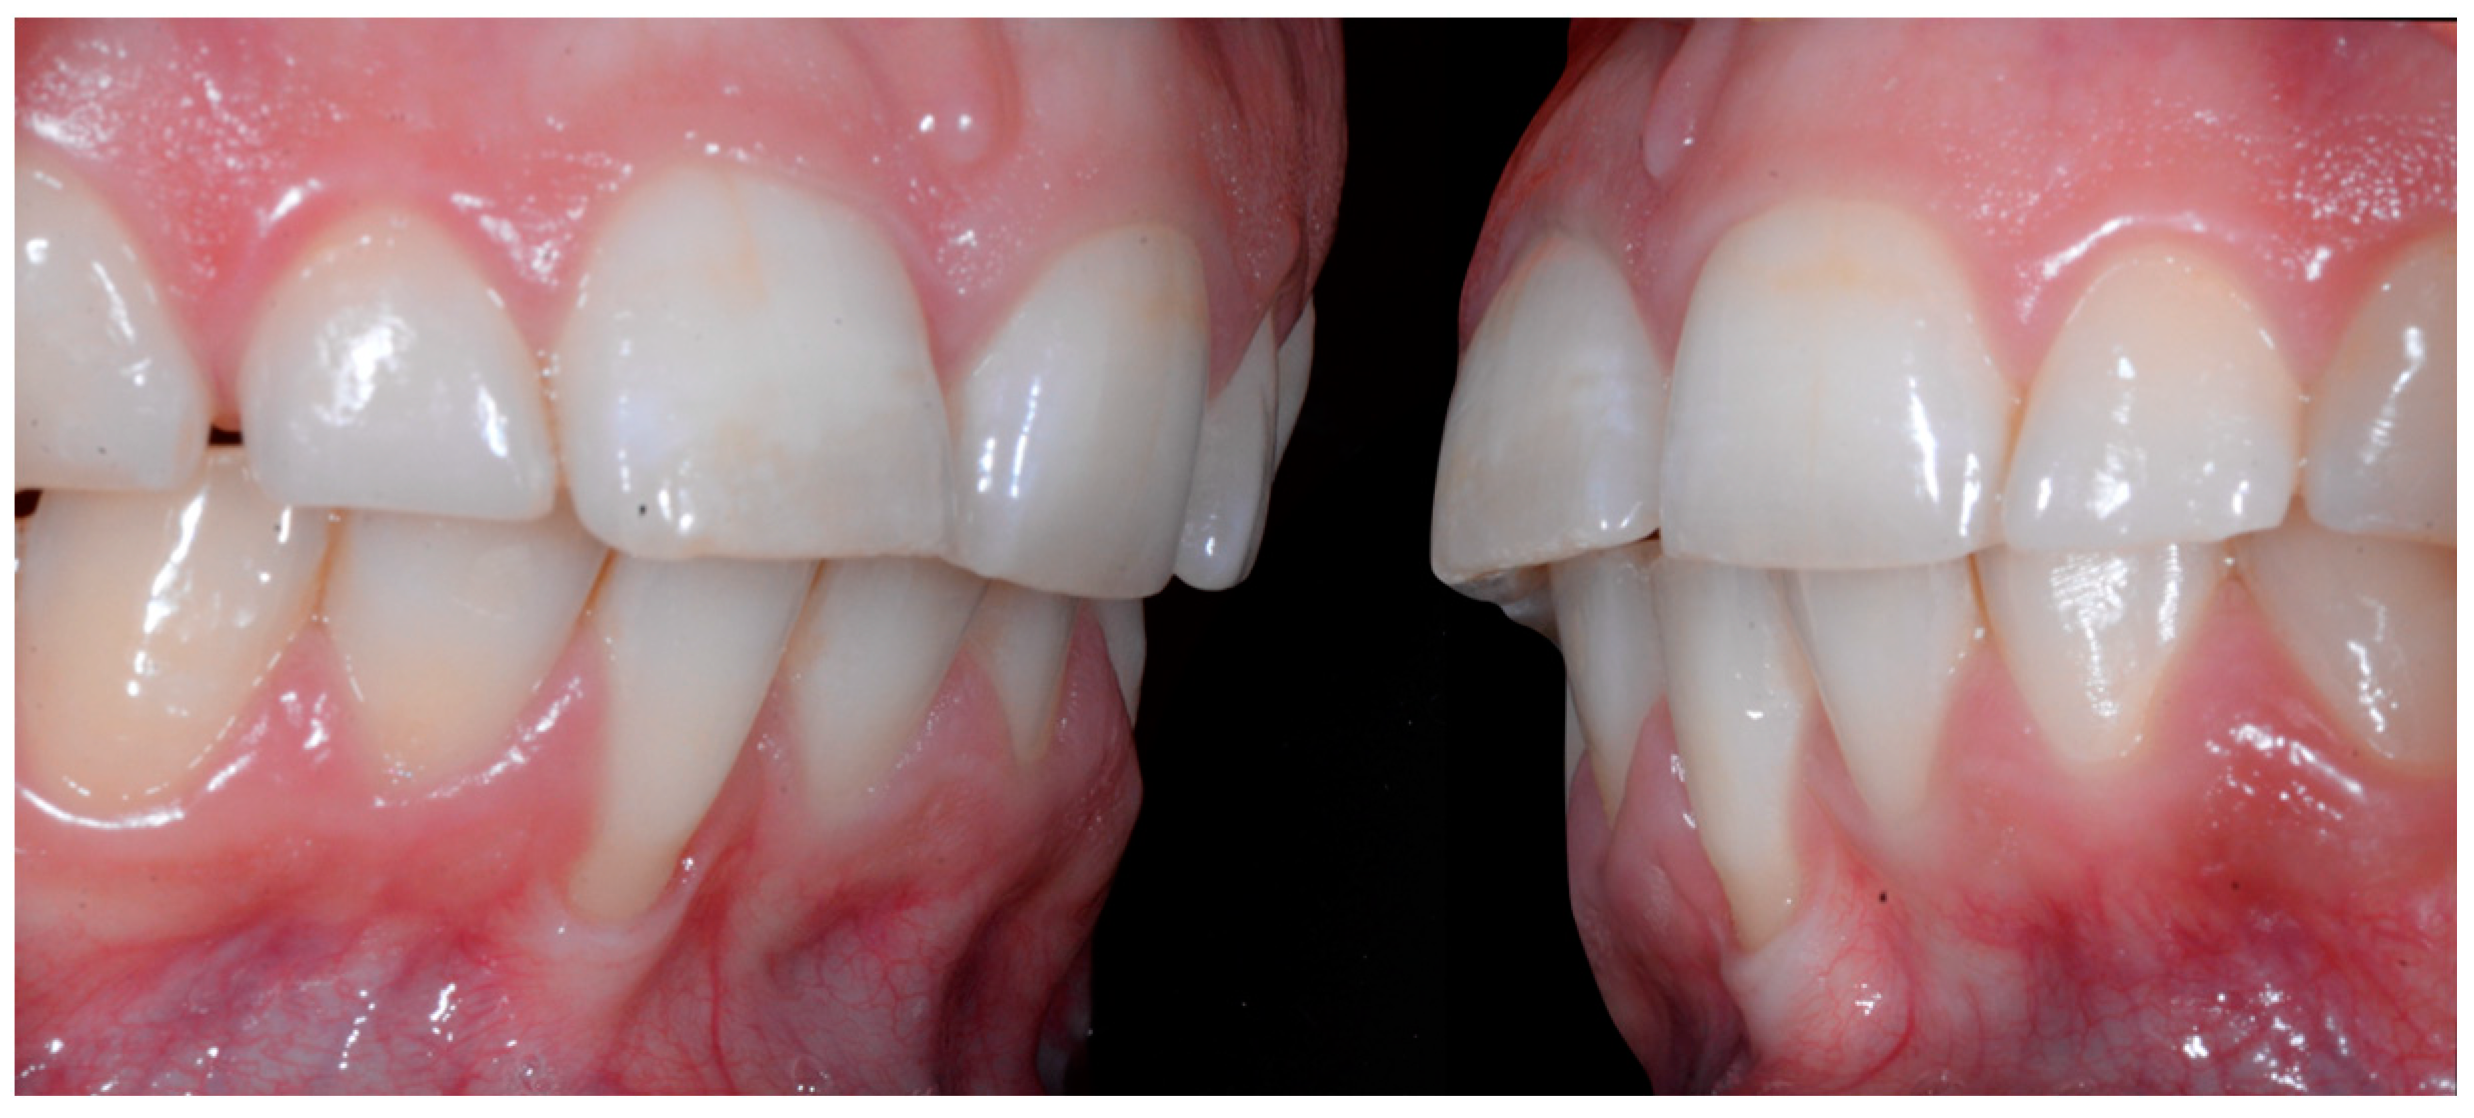

A 26-year-old female patient was referred by her general dentist for suspected wire syndrome. Orthodontic treatment had been performed 10 years previously, and bonded restorations had been fitted at the end of the treatment. The patient mentioned several episodes of breakage/adhesion, without further details. She has good oral hygiene and a right and left Class I (Figure 5).

Figure 5.

Intermediate wire syndrome. Frontal and lateral views.

In Figure 6, 11 and 21 show a difference in incisal edge height and gingival margin. Tooth 41 shows gingival recession to the muco-gingival junction (Cairo’s RT1) with root visibility. Tooth 33 had a significant lingual tilt (coronal–lingual torque), not symmetrical to tooth 43.

Figure 6.

Intermediate wire syndrome. Frontal view.

The root of tooth 21 is visible through the gingiva (Figure 7). Figure 8 shows the extent of gingival recession on tooth 41.

Figure 7.

Intermediate wire syndrome. Lateral view.

Figure 8.

Intermediate wire syndrome. Lateral views.

The occlusal views provide additional relevant information (Figure 9 and Figure 10). A maxillary retainer was present on 11 and 21 only and a difference in visibility of the vestibular surfaces (differential torque) on these same teeth was noted.

In the mandible, the retainer was broken distal to 42 and, despite being intact on 33, this tooth had increased visibility of its vestibular surface compared to its contralateral tooth (differential torque). Finally, teeth 31 and 41 also showed a difference in the visibility of their vestibular surfaces (differential torque). Ultimately, the patient was diagnosed with an X-effect wire syndrome on 21, an X-effect wire syndrome on 41, and a Twist-effect wire syndrome on 33.